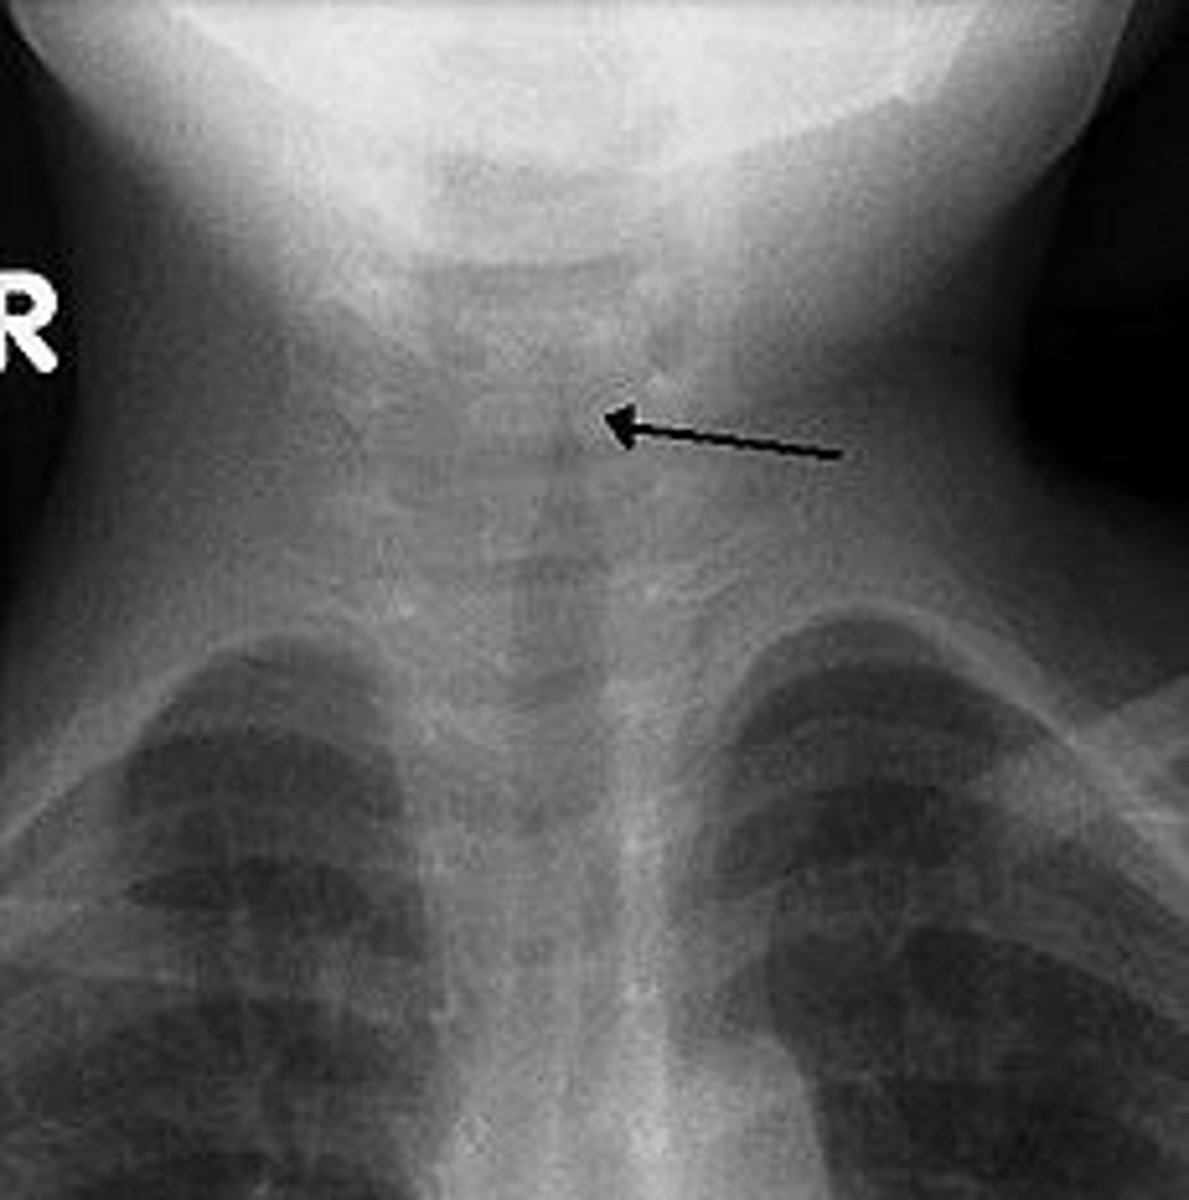

steeple sign

Subglottic stenosis or narrowing of the opening below the vocal folds is a classic sign of croup.